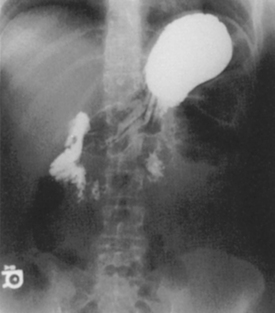

Fig. 9-31 AP supine Trendelenburg, upper GI (stomach) (Trendelenburg position best demonstrates hiatal hernia).